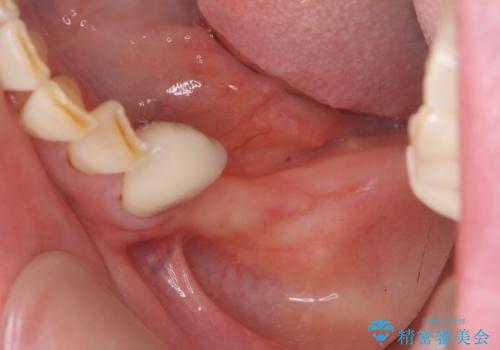

- 歯を虫歯により失い、「とりあえず入れ歯を入れたが,とにかく噛めず食事が全く楽しくない」またしっかりと噛みたいと希望され来院されました。

入れ歯を外し、またしっかりと噛んで食事を楽しめるようになるためにインプラントによる治療を計画します。

インプラントを埋入することで入れ歯のように取り外しをする必要がなくしっかりと噛めるような状態になり、大変治療結果に満足していただくことができました。